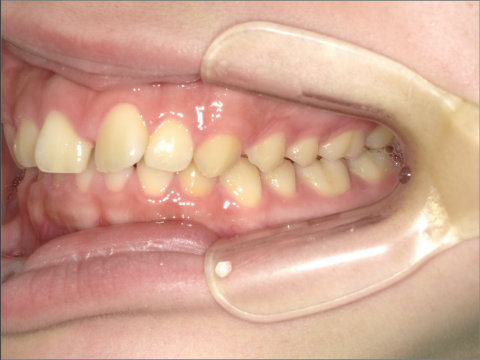

ご年齢 35歳男性

治療期間 2022/08/22〜2023/03/24(1年5ヶ月)

診断 110,000円(税込)

アライナー 550,000円(税込)

リテーナー 55,000円(税込)

BEFORE

AFTER